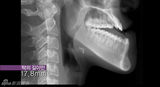

中国少女郭方圆因下颌出奇长常常被嘲笑,还被戏称“外星人”,日前通过韩国整容节目重拾美丽,变成让人既羡慕惊讶的芭比娃娃。视频:中国恐龙女韩国整容变芭比(2013-09-06 / sina)